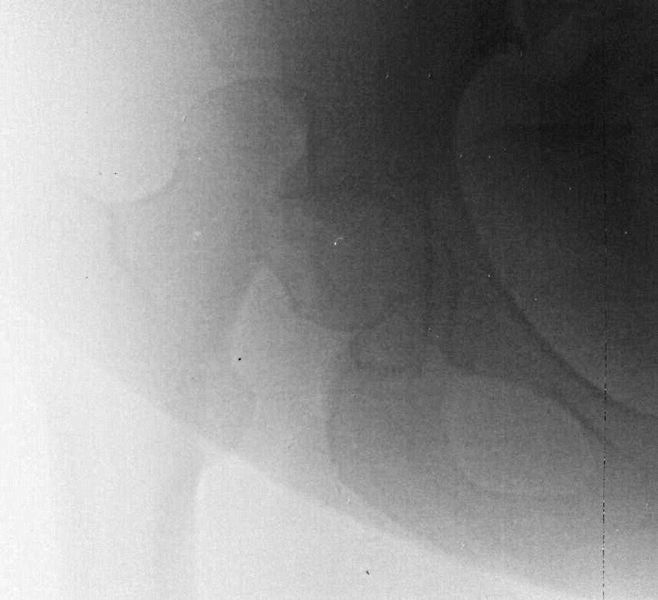

За праздники поступил еще один Pipkin IV. Женщина 30 лет, пострадала в ДТП

(пассажир). Сочетанная травма (ISS 25). Множественные переломы ребер с двух

сторон с пневмотораксом  и пневмомедиастинумом. Закрытый перелом пилона

справа. Задний переломо-вывих головки правой бедренной кости (Pipkin IV).

Ожирение III- IV  степени. Пацинентка в реанимации, состояние остается

тяжелым.

Задренировали плевральные полости, наложили АНФ на дистальный отдел правой

голени и произвели закрытое вправление вывиха бедра + скелетное вытяжение

правой нижней конечности в день поступления. КТ контроль показал довольно

сносную картину результата репозиции. Отломок головки оставался в полости

сустава во время вывиха, т.к. видимо сохранилось прикрепление со связкой.

На КТ остается широкой суставная щель, что косвенно может указывать на

интерпозицию мягкими тканями, либо "встать на место" мешает медиальный

отломок головки.